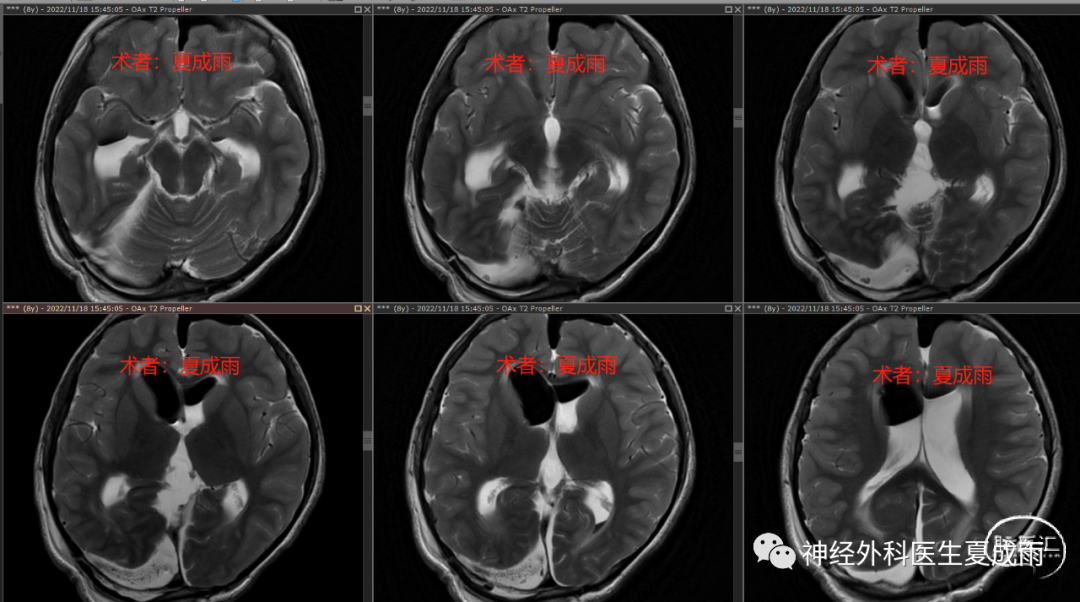

术前及术后24h磁共振对比⏬

术后24h磁共振T2⏬

(未见明显脑挫伤)